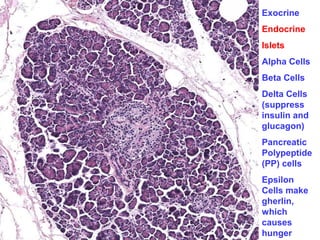

High mag of an Islet – note Beta cells and more eosinophilic Alpha2 cells

Exocrine

Endocrine

Islets

Alpha Cells

Beta Cells

Delta Cells

(suppress

insulin and

glucagon)

Pancreatic

Polypeptide

(PP) cells

Epsilon

Cells make

gherlin,

which

causes

hunger

• β cell produces insulin,

• α cell secretes glucagon,

• δ cells contain somatostatin, which suppresses both

insulin and glucagon

• PP cells contain pancreatic polypeptide that exerts

secretion of GIT enzymes and inhibits its motility.

• D1 cells elaborate vasoactive intestinal polypeptide

(VIP), that induces glycogenolysis and hyperglycemia;

• Enterochromaffin cells synthesize serotonin and are

the source of pancreatic tumors that cause the

carcinoid syndrome